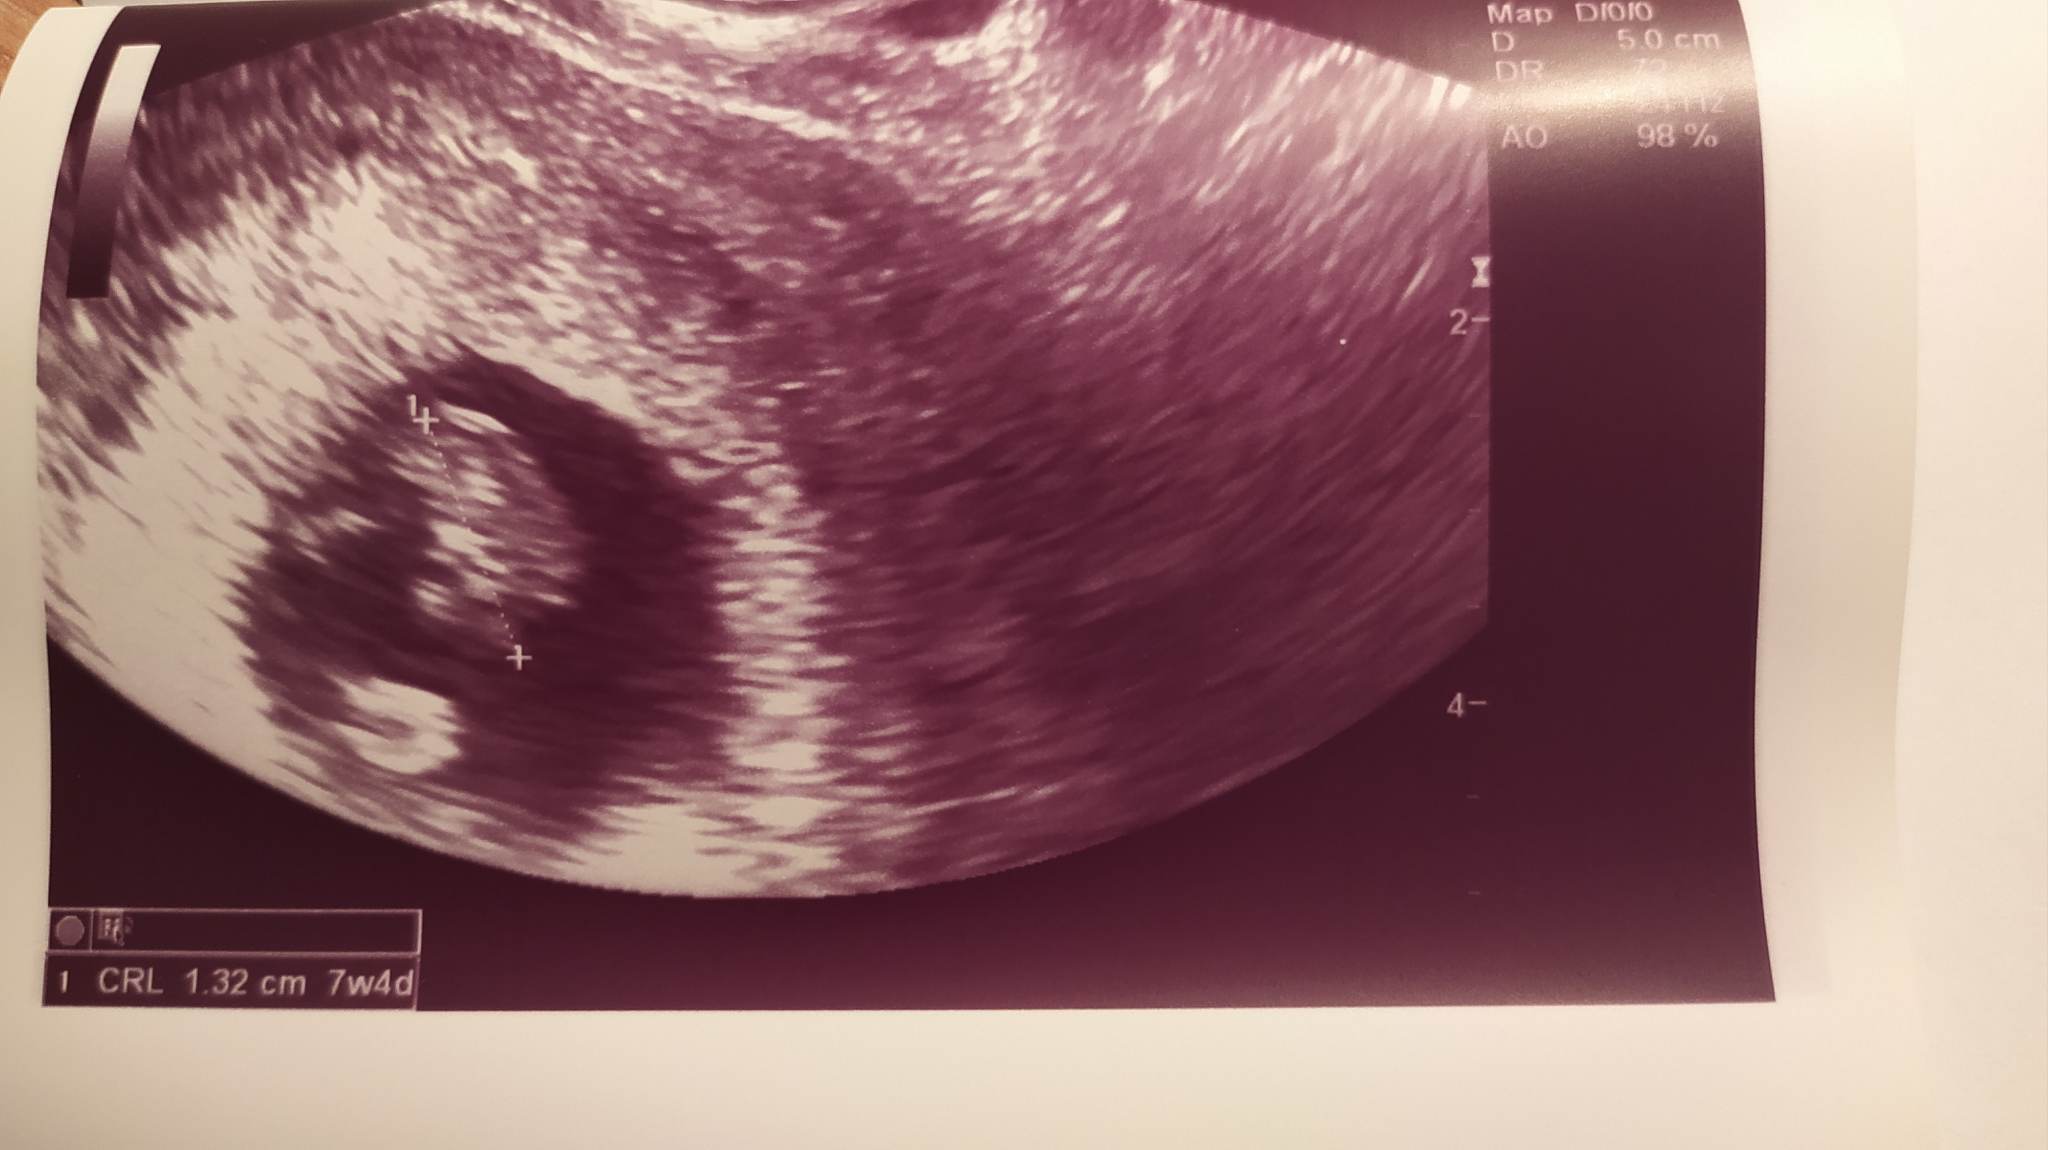

Dobry wieczór, jestem po wizycie, jest wszystko ok, wiek ciąży z om 7+5 a z usg 7+4 i to by się pokrywało z terminem owulacji, termin porodu 18.08. Widok serduszka mega wzruszający ;)

A mam :) Niestety jakość nie powala ale widzę tam zarys dzidziusia, mój stary powiedział że widzi plamę :p Widziałaś już serduszko czy to będzie pierwszy raz? :)

Echo zarodka słyszałam na wcześniejszej wizycie, bodajże na 5+6. Moja pani doktor ma bardzo fajne USG i dużo widać. Tydzień temu byłam na Luxmed, żeby badania krwi załatwić, to fasolka miała jeszcze niecały 1cm 😃 U Ciebie tez już sporo widać, powoli się kształtuje dziecię ;)